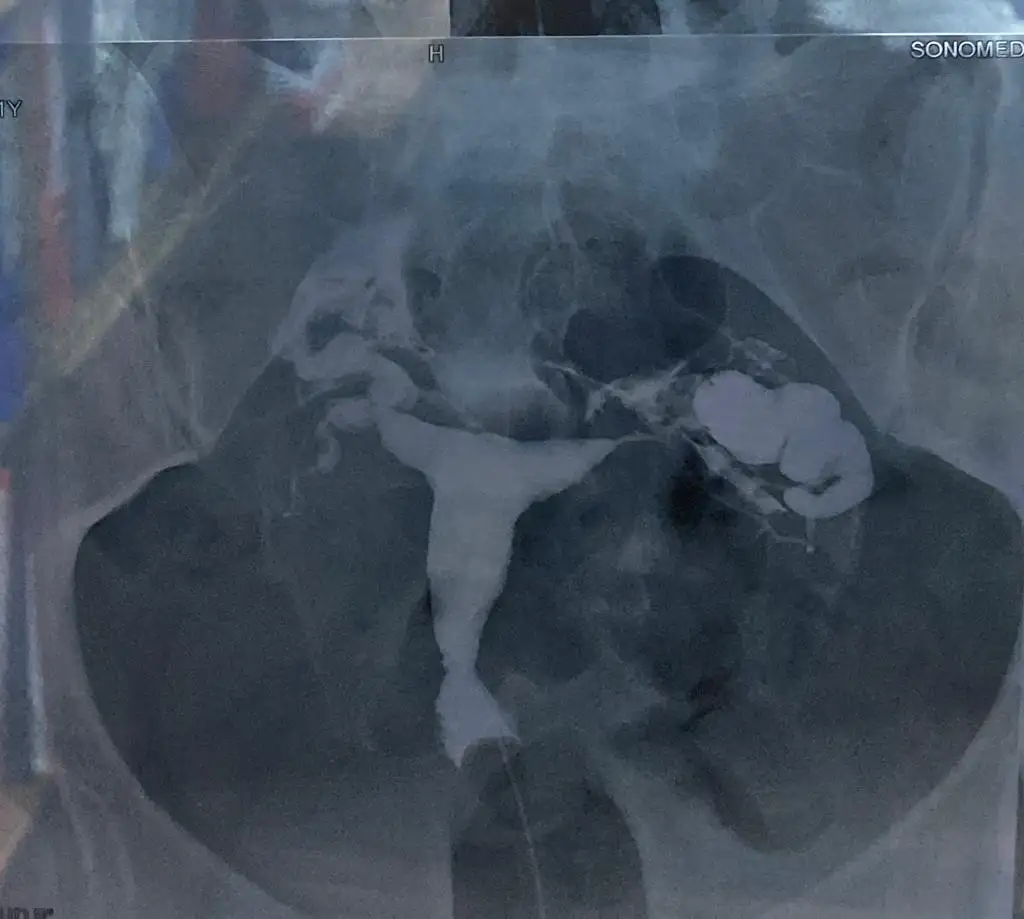

Selam canım sana örnek olması acısından kendi filmimin goruntusu seninki bence normal ben herhangi bir şişik gormedm

Şey gibi hani şiş duran kısım yaniBenmimkini açamadım neden bilmiuorum cd denama sağ görüntü ayni benim sol tüpe benziyor o dimi hidrosalpinks olan Ekin?

Görüntülerimin sol kısım gibi olmadığıma ben de eminim. Sağ biraz borumsu benim de sol kısmın ucu dikkatli bakarsanız o şekilde benzetim yapabilirsiniz ondan didikledim ama sağ kısma temiz demişler sizin çok sağ olun bana fikir oldusol hidrosalpenks laparoskopi ile alındı komple sag laporoskopide temiz cıktı ellenmedi o yüzden

EVET EVET bakınca direk sagda kalan kısım sol tüpŞey gibi hani şiş duran kısım yani

tamam aynı o zaman senin kiEVET EVET bakınca direk sagda kalan kısım sol tüp